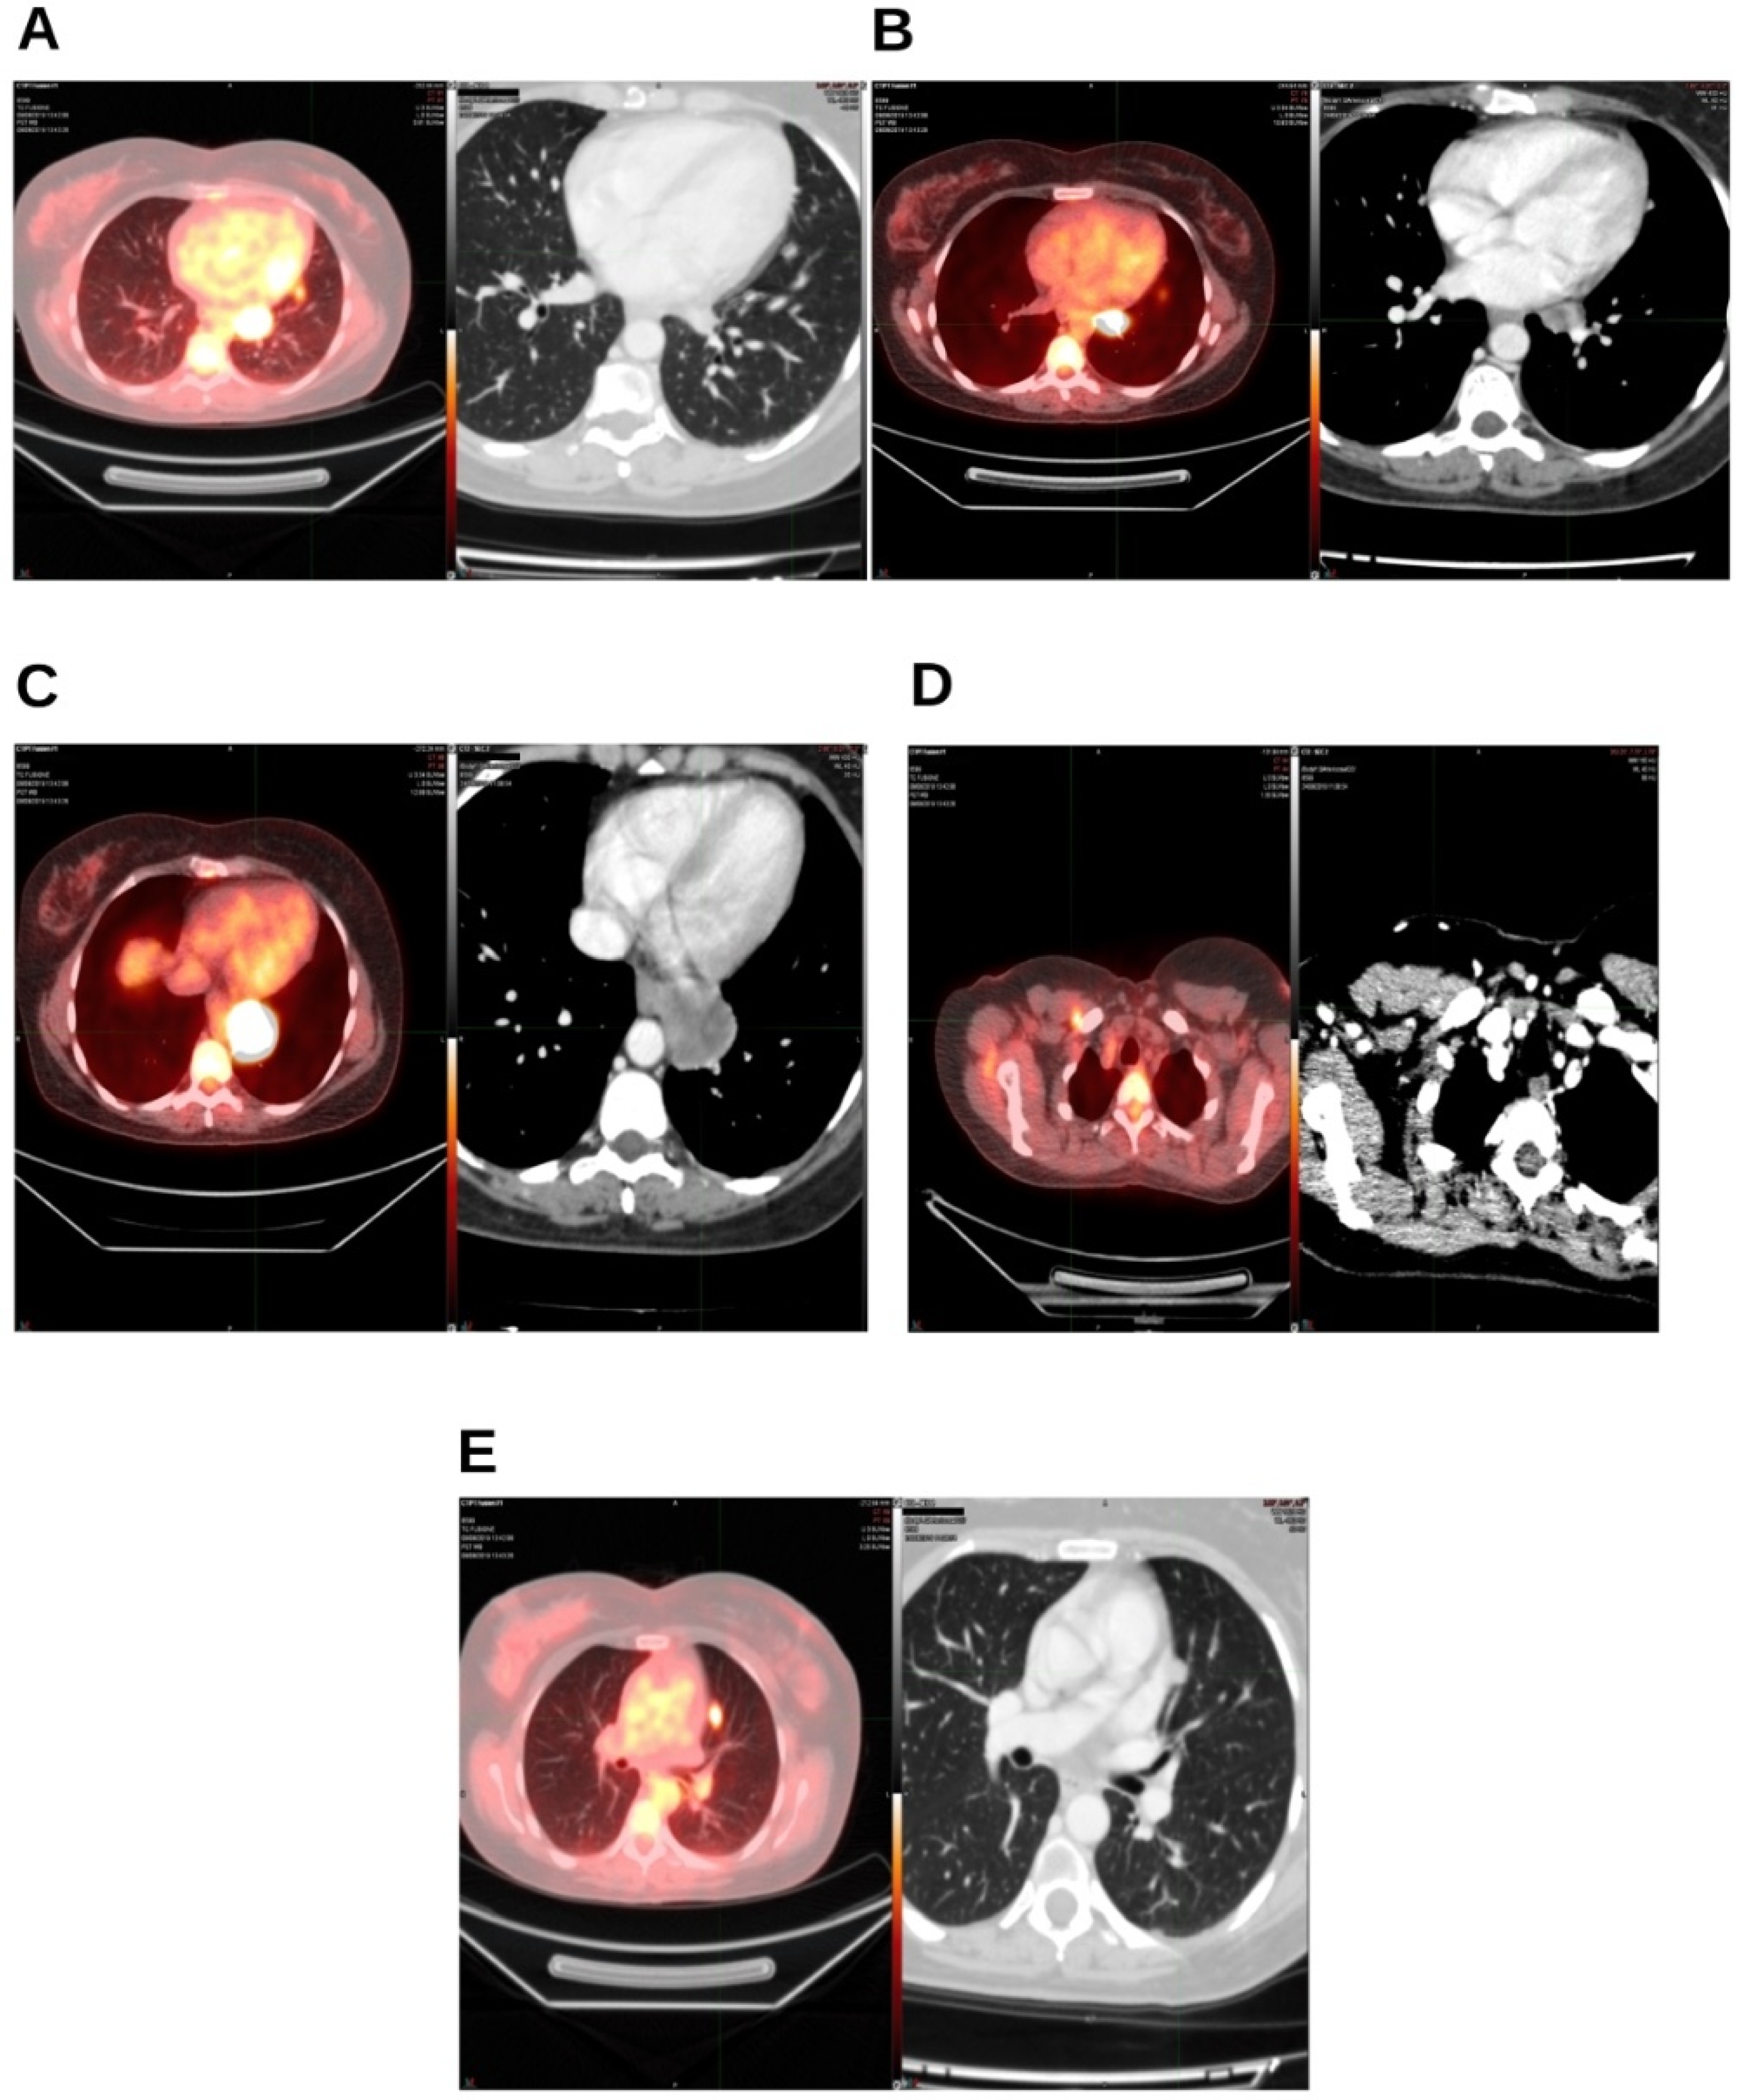

2. Case Presentation